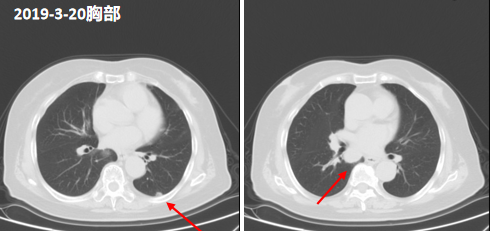

2020-3-20胸部CT:1.两肺下叶多发结节,较前(2019.09.11)部分增大,转移考虑。2.两肺少量纤维灶,右肺上叶钙化灶。3.主动脉瓣区钙化。